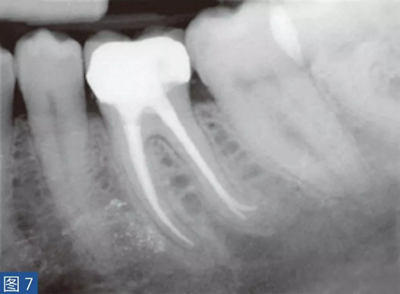

致密性骨炎(圖6 和7)是AAP 的一個(gè)變種。造成致密性骨炎的原因是,根尖周組織受到長(zhǎng)期的持續(xù)性刺激。臨床檢查時(shí),對(duì)敏感測(cè)試、叩診和觸診可能有反應(yīng),也可能無(wú)反應(yīng)。放射學(xué)檢查,牙齒的根尖周圍存在彌漫性的致密阻射影像。

圖7:36 牙齒CO。根管再治療12 個(gè)月后。